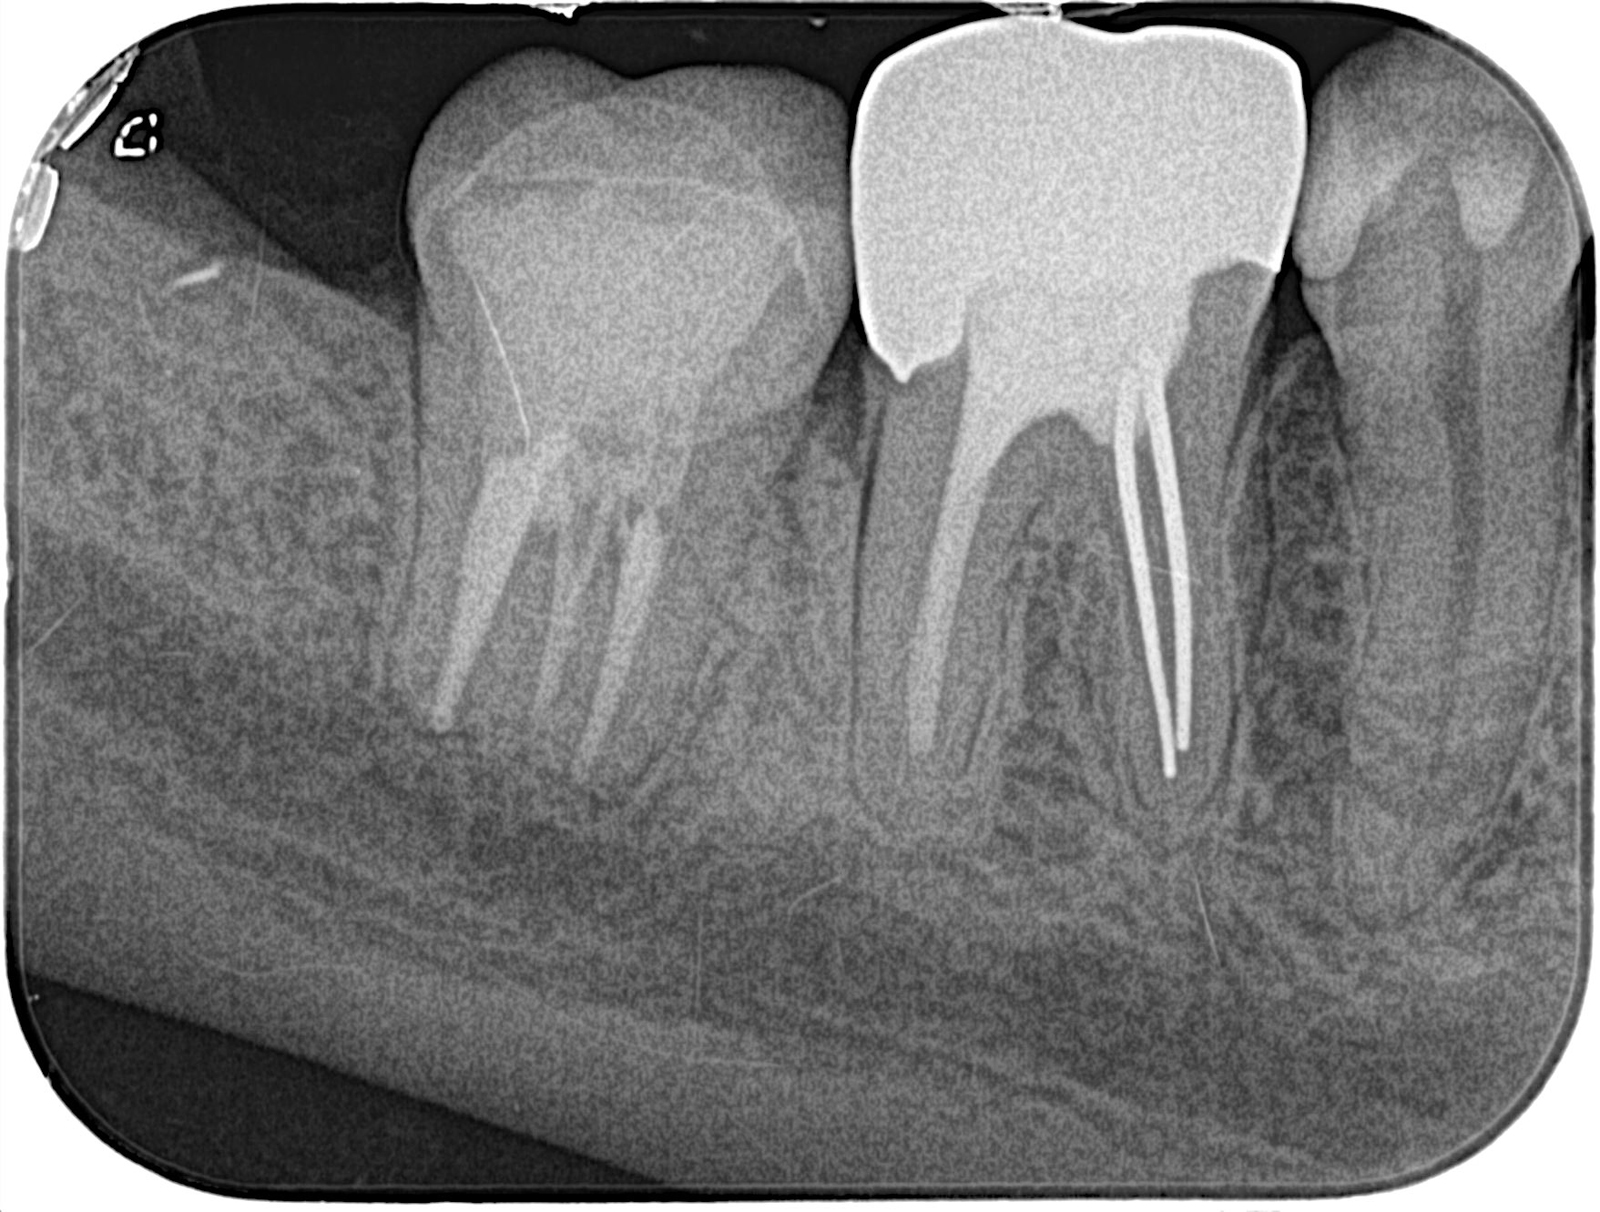

次の写真をご覧ください。歯の中を走る黒い筋が、「根管」です。

根管の中は非常にせまく複雑です。直径が1mmに満たないところもあります。「根管治療」では、こんなに狭くて複雑な根管内から、虫歯菌に感染した神経を取り除きます。

「CT」で複雑な根管を的確に可視化

根管は歯の内部にあり、肉眼で確認することはできません。そのため、根管の詳細を把握するにはX線検査が欠かせません。一般的には「レントゲン」が知られていますが、私たちは「CT」を用いた検査を行っています。レントゲンは2次元の画像しか得られませんが、CTはお口の周囲を回転しながら撮影し、立体的で精細な画像を提供します